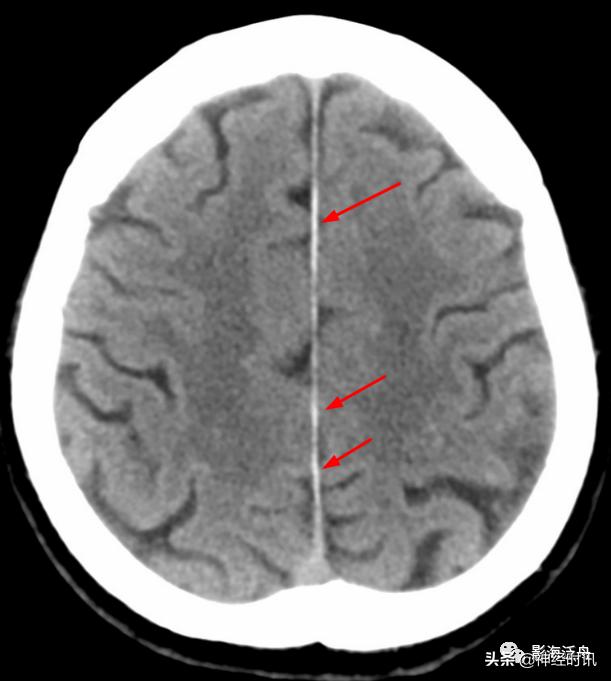

闭合性头颅外伤后,患者双侧大脑半球的多个脑回出现挫伤(红箭),损伤脑组织邻近的脑沟、脑裂少量积血,此即蛛血。由此可见蛛血的本质是脑表层(即脑灰质)挫伤后,血液沿破损的软脑膜流入到蛛网膜下腔,并在血清蛋白收缩作用下凝聚所致。也就是说,在凝血功能正常的情况下,程度较轻的外伤性蛛血引发大出血的概率极低。